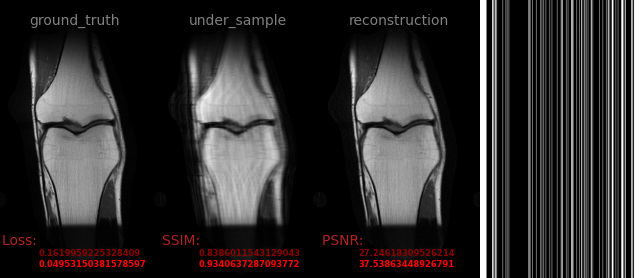

AVS-Net

Image-to-Image

medical